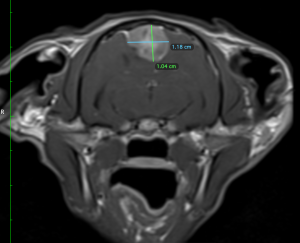

Violet has a very dedicated owner and she wanted to do everything she could. She agreed to a surgical approach to Violet’s treatment plan. The next step was to undertake an MRI scan for surgical planning. MRIs can provide a much more detailed picture of the central nervous system. The MRI scan confirmed a mass in the midline of the cerebrum. Given the appearance and location, this was highly likely a tumour known as a meningioma. This is a tumour of the meninges (the outer membranes of the brain).

Meningiomas are the most common brain tumour found in cats and are generally benign, having a tendency to cause local compression as they grow, rather than spreading to other parts of the body. In Violet’s case, as her brain tumour grew, she started to show clinical signs, affecting her neurological function. This is because there is a limited amount of space within the skull and when the tumour grows it compresses surrounding brain tissue. With Violet, the tumour had grown to such a size that her cerebellum had herniated through the back of her skull (arrows).